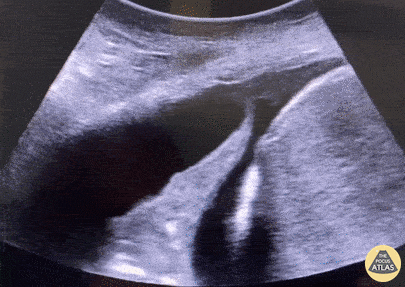

Right lower lobe pneumonia with lobar atelectasis and pleural fluid accumulation. These ultrasonographic findings are collectively referred to as jelly fish sign. This anechoic parapneumonic effusion measured 2.5 cm on ultrasound, and chest tube insertion resulted in drainage of 800 mL of clear fluid. Gábor Csupor